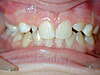

Le cas ci-dessus présente une adolescente ayant les 2 incisives latérales supérieures manquantes (absence congénitale/anodontie).

Après consultation avec le dentiste généraliste, il fût décidé d’ouvrir les espaces des latérales manquantes et de les faire remplacer prothétiquement après le traitement d’orthodontie effectué avec des multibagues.